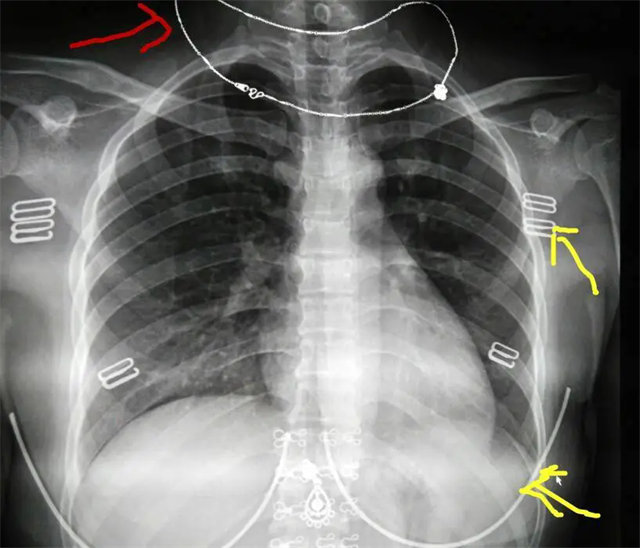

拍攝的不合格胸片的缺陷和解決方法

缺陷:雙側(cè)胸鎖關(guān)節(jié)不對稱,且有手機顯影。

解決:去除手機后,使患者左側(cè)緊貼成像件曝光。

缺陷:左肩胛骨部分與左肺野重疊。

解決:使患者左肩旋前緊貼成像件重新曝光。

缺陷:肩胛骨未完全拉離肺野,吸氣不完全,存在金屬偽影遮擋,略有聳肩,且肺尖顯示不好,圖像顆粒感較強,管電流量不夠,信噪比偏低。

解決:去除金屬物品后,按標準體位,使患者雙肩旋前與前胸一并緊貼成像件,適當(dāng)調(diào)高mAs,然后深吸氣后屏氣曝光。